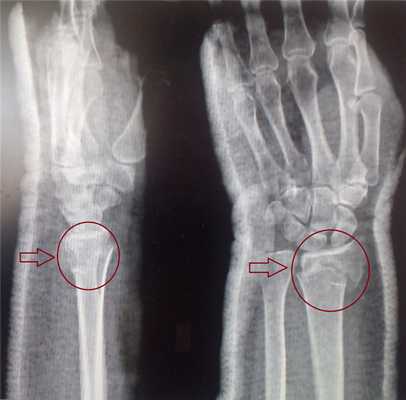

Большинство переломов дистального отдела лучевой диагностируются обычной рентгенографией в 2-х проекциях. Компьютерная томография (КТ) необходима при внутрисуставных переломах.

Для подтверждения диагноза выполняются рентгенограммы лучезапястного сустава в 2-х проекциях. Рентген являются наиболее распространенным и широко доступным диагностическим методом визуализации костей.

На представленной рентгенограмме не тренированный глаз может вообще не увидеть перелома, хотя врач травматолог и квалифицированный рентгенолог заметят насколько «просела» суставная поверхность лучевой кости, и отметят, что она развёрнута в тыльную сторону на 10 градусов (в норме она должна смотреть в ладонную сторону). Если присмотреться повнимательнее становятся видны линии перелома.

Для уточнения характера перелома и выбора дальнейшей тактики лечения используется рентгенография, в ряде случаев - компьютерная томография. Иногда требуется УЗИ кистевого сустава.